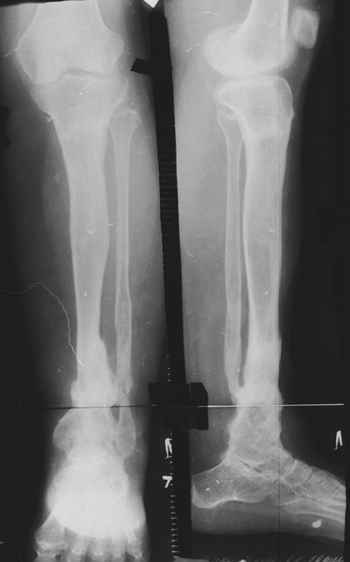

Случай, который я представляю, был сделан мной около 20 лет назад в Кургане.

Женщина 28 лет, пошедшая 13 предыдущих оперативных вмешательств по-поводу ВПБ имела 9 см. укорочения.

На первом этапе аппаратом Илизарова закрыто устранена деформация голени.

На втором этапе произведёно освежение краёв костных фрагментов б/б и м/б костей с приданием проксимальному фрагменту б/б кости впалой, а дистальному выпуклой формы, открытие канала проксимального фрагмента и погружной остеосинтез, а также остеотомия б/б кости в в/3 и м/б кости на границе с/3 и н/3 голени. Больной проводился одновременный бифокальный компрессионно-дистракционный остеосинтез. Достигнуто 11 см. удлинение и сращение ВПГ.

Срок лечения 11 месяцев. Наблюдение 2 года.